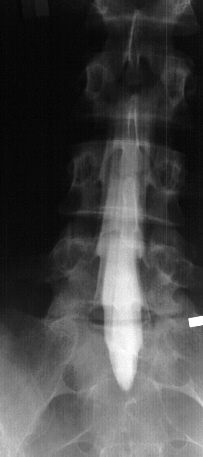

Radiological Evaluation

- plain x-rays normal, with mild spinal curve

- MRI-L5-S1 Right disc herniation with nerve root impingement

- Myleogram reveals nerve root impingement